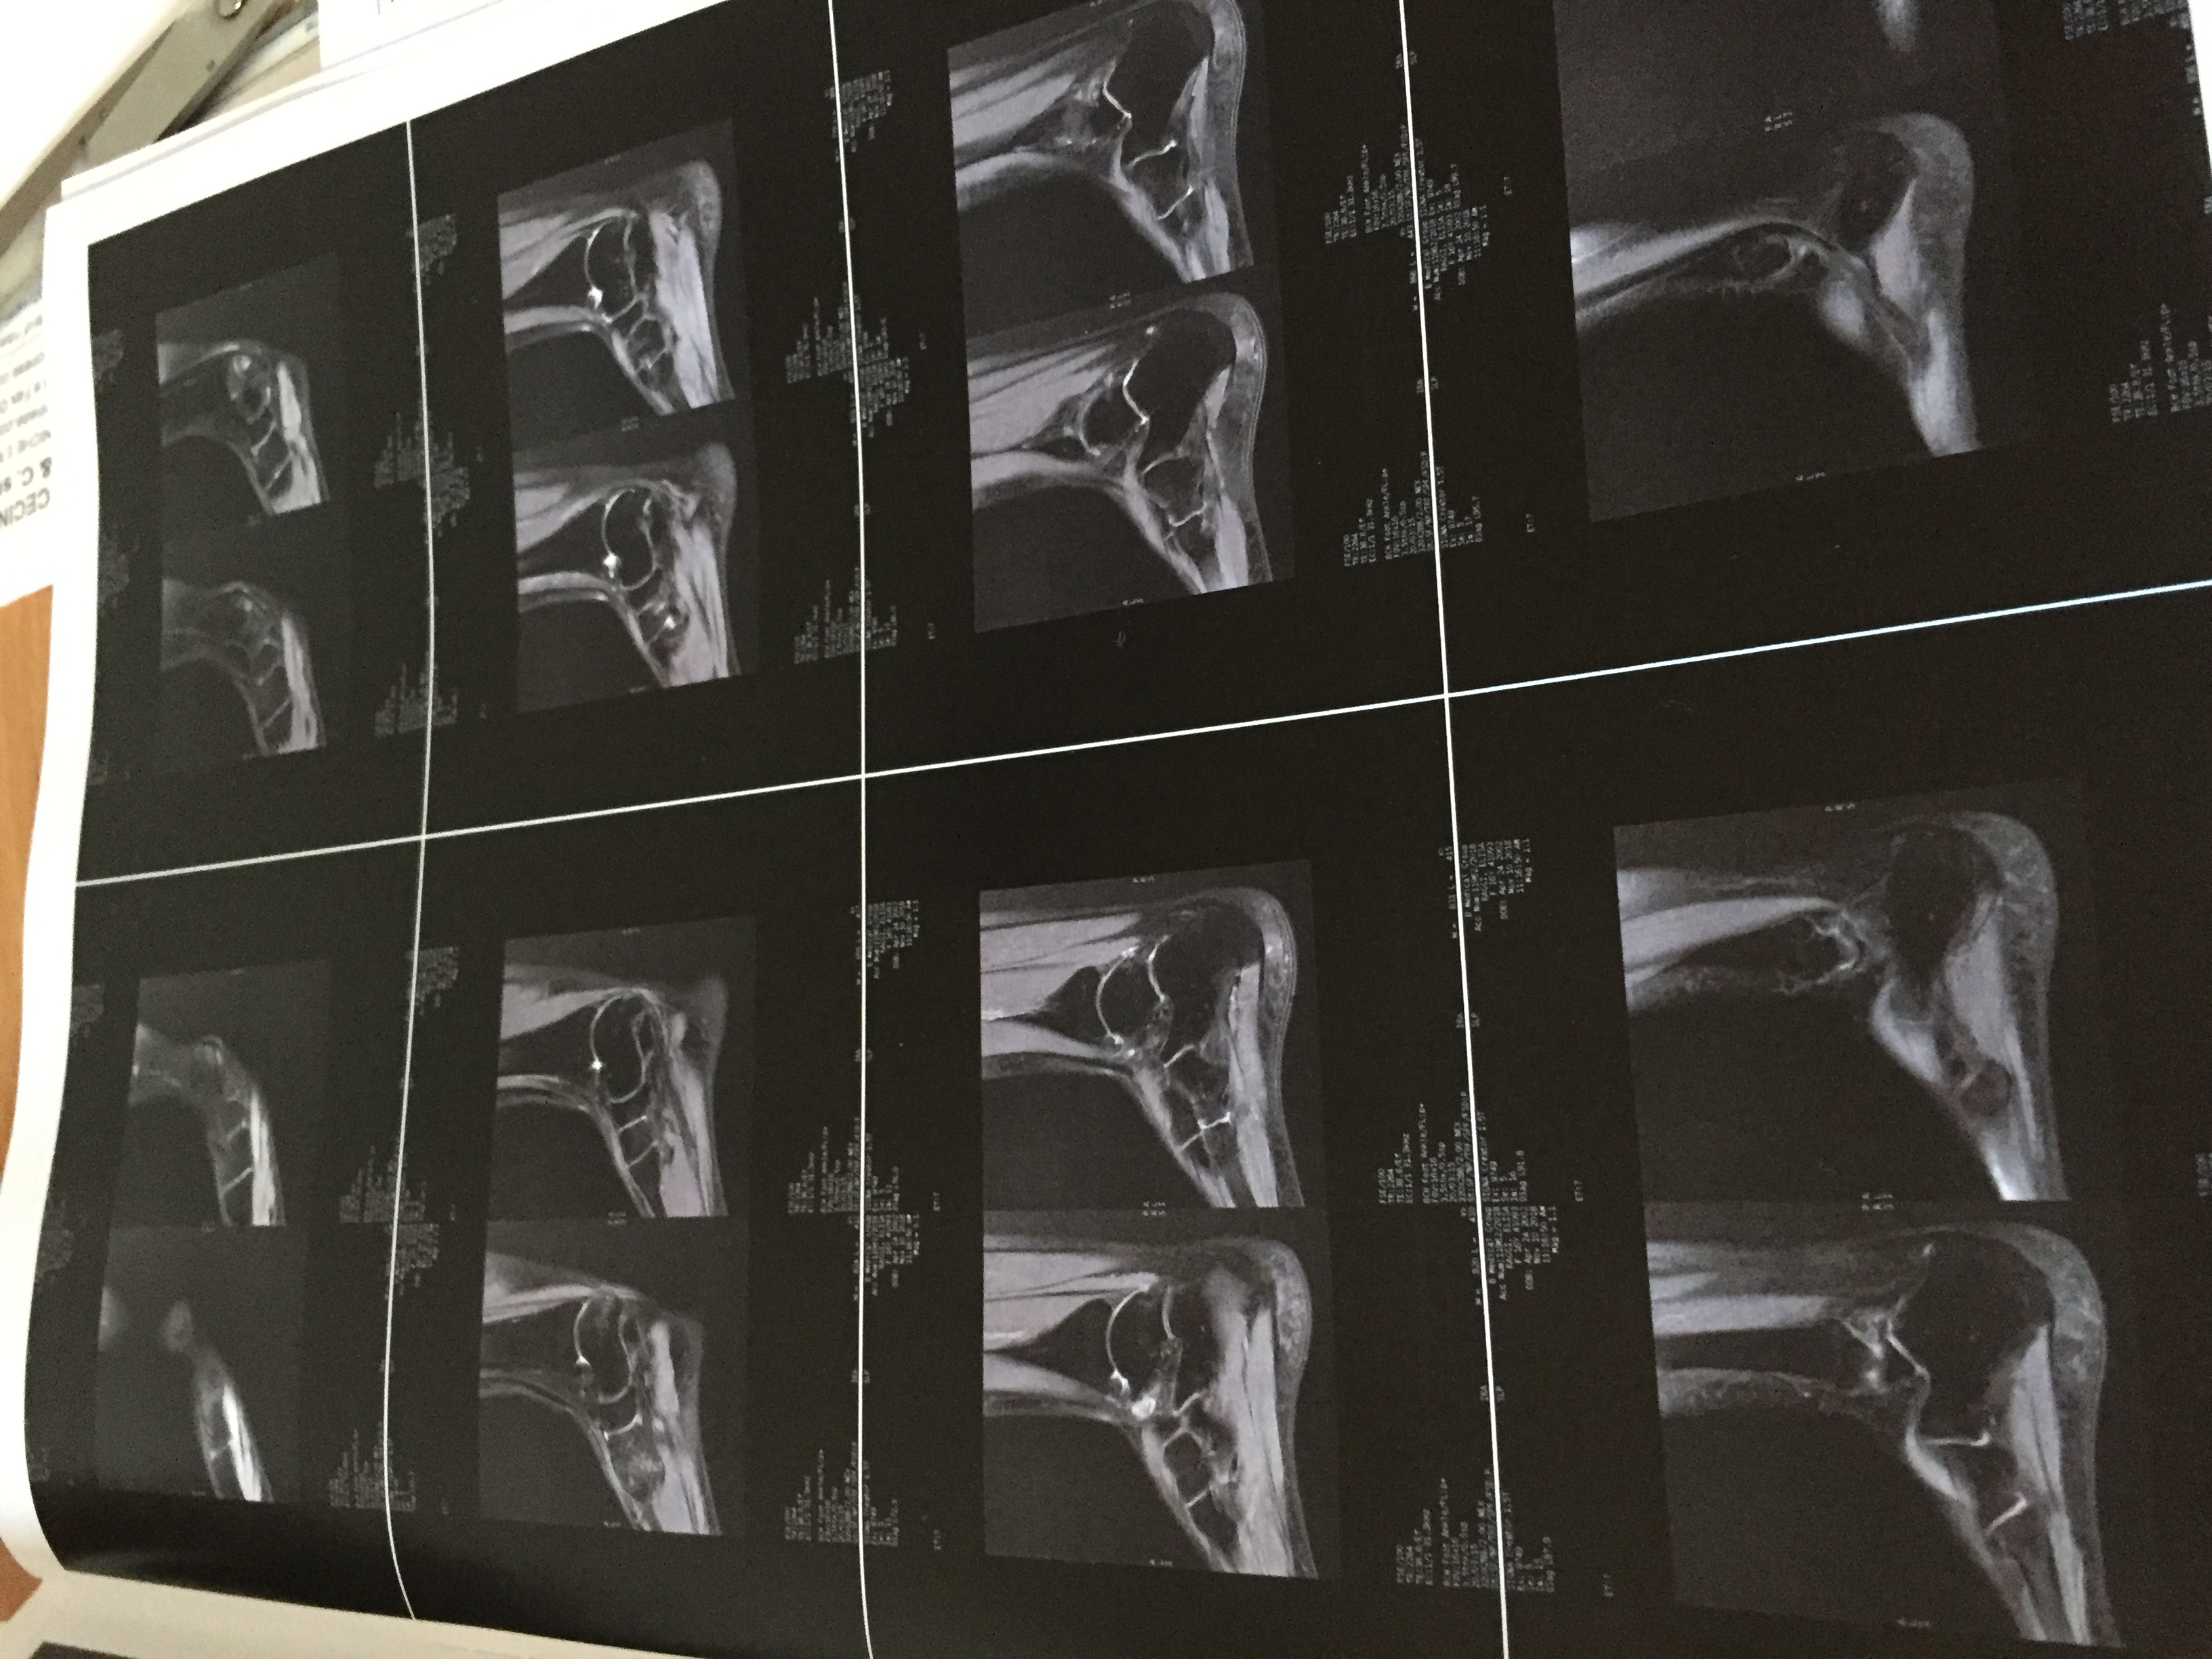

Buongiorno mia figlia ginnasta è circa 1 mese che dolore all collo del piede dopo 17 laserhag poco miglioramento

Le invio delle foto della rm , può darmi informazioni?

9D220D31-C5F4-4D53-B313-ACBB0C1CAF8F.jpeg

[ 1.41 MiB | Osservato 750 volte ]